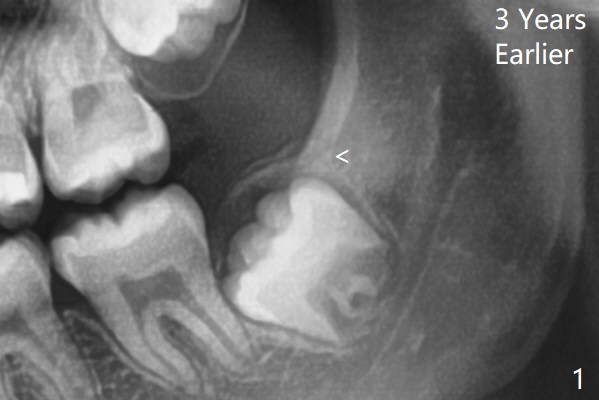

14岁外斜嵴尚未完全形成(图一:箭头);17岁时外斜嵴近中部分仍然被智齿阻挡而没有形成或者去除颊侧骨板时失去(图四),但是密度增加。这两个智齿不位于第二磨牙颊侧。